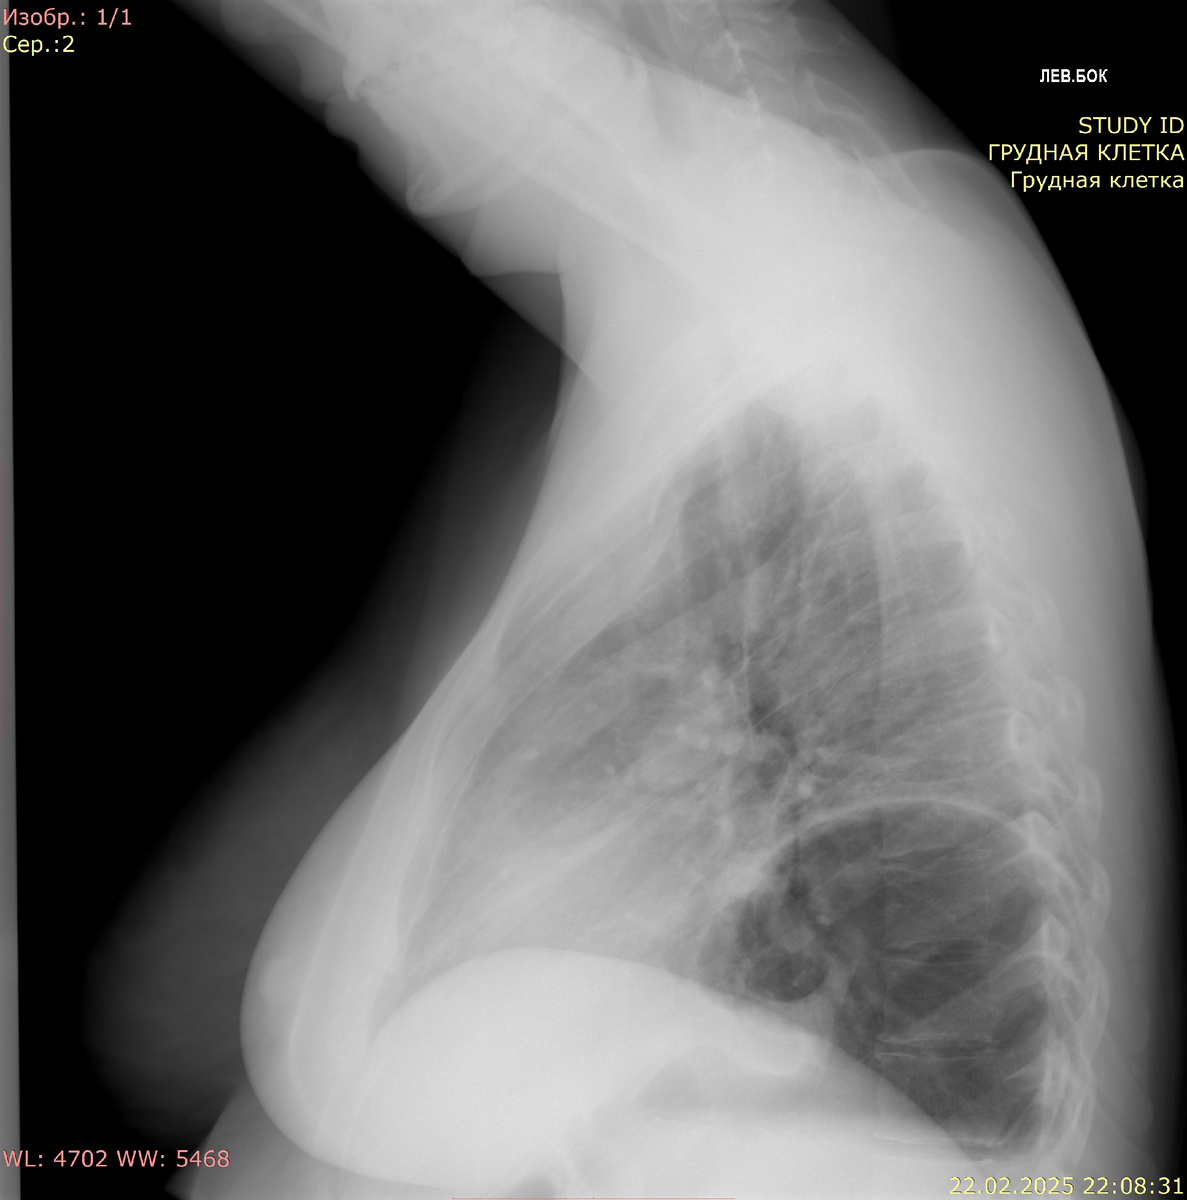

Рентгенография органов брюшной полости в прямой проекции:

В проекции грудной полости слева под куполом диафрагмы визуализируется желудок с уровнем "жидкость-газ", диаметр 10 см. Под куполами диафрагмы свободный газ не определяется.

Заключение: данных за свободный газ не получено. Картина может соответствовать диафрагмальной грыже (содержимое - желудок).